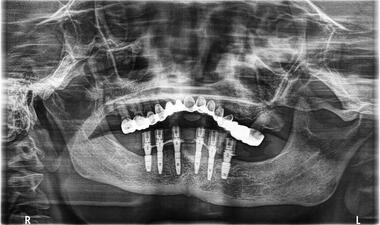

術中

下顎缺牙,植入六顆植體